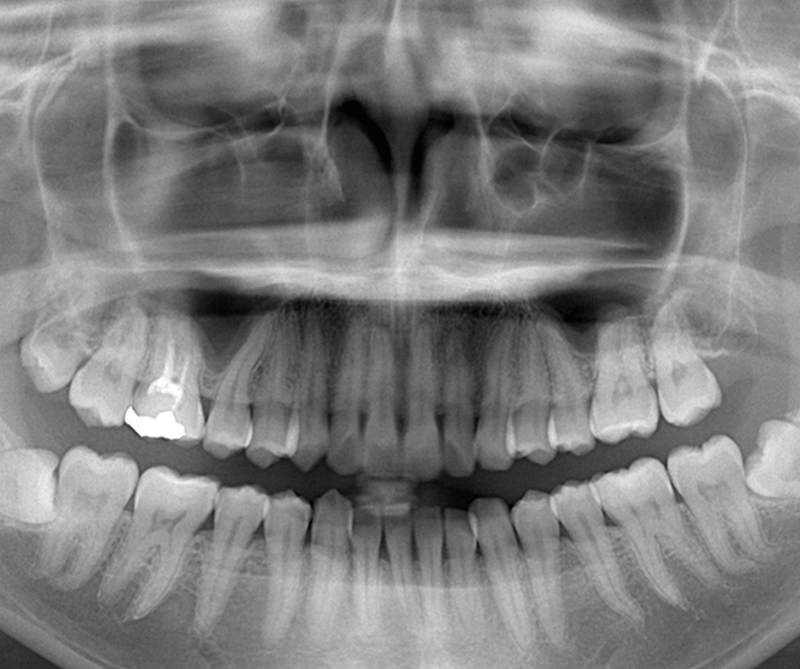

親知らず専門の歯科医師がいることをご存知でしょうか。当院では10年以上総合病院に在籍した日本口腔外科学会認定医があなたの抜歯を担当させて頂きます。

専門性の高い処置だからこそ、実績のある歯科医師のみが対応し、安心安全の抜歯を提供致します。